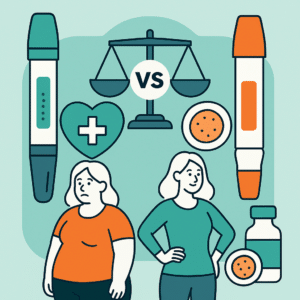

Mounjaro vs Ozempic: Which Weight Loss Treatment Is Right for You?

If you have been looking for new ways to lose weight, there…

Weight Loss Medications: Comparing Top Options

Weight loss medications like Mounjaro (tirzepatide) and Ozempic (semaglutide) have gained popularity…